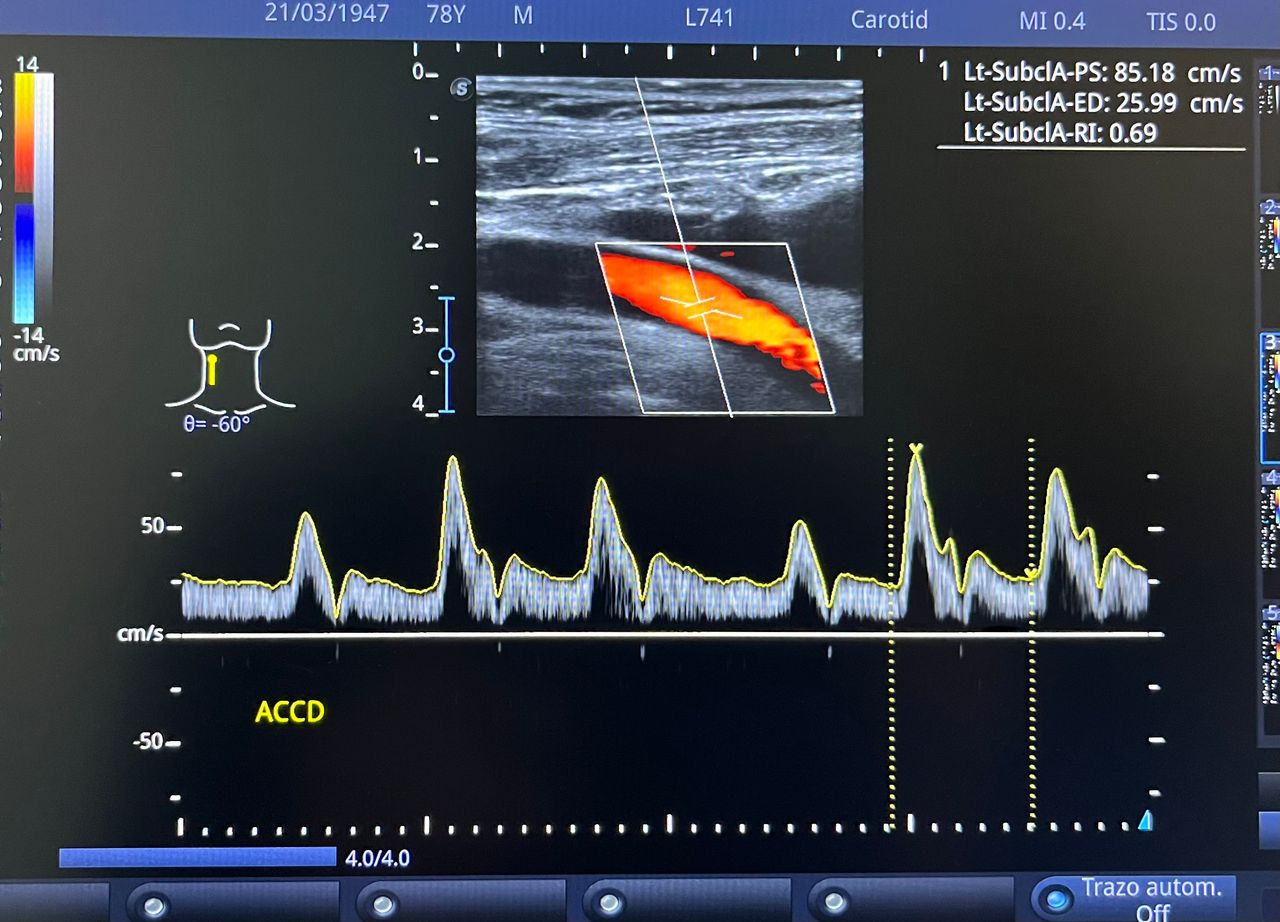

Médico general con 15 años de experiencia, master en enfermedades infecciosas y antibioticoterapia por parte de la Universidad Cardenal Herrera en Valencia, ademas de diversos diplomados en el área de Infectología y Parasitología, Urgencias, Imagenología y Medicina del Trabajo. He laborado en Hospitales y Clínicas en el área de Urgencias, en Laboratorios realizando estudios de Imagen, en especifico ultrasonidos de todo tipo desde básicos hasta avanzados incluidos los obstétricos estructurales, en Secretaría de Salud del Estado de Querétaro realizando ultrasonidos obstétricos para la detección de malformaciones en los tres trimestres del embarazo en diversos centros de salud, como médico de Empresas en el campo de Salud Laboral y actualmente en este consultorio en donde para su mejor atención y siempre buscando integrar la mayoría de las herramientas diagnosticas cuento con equipo de ultrasonido como apoyo en la exploración del paciente o como servicio diagnostico por imagen, realizo ultrasonidos convencionales (hepatobiliar (hígado, páncreas, vesícula y bazo), vías urinarias, ginecológico abdominal y transvaginal, tiroideo, prostático, testicular, pared abdominal) y especializados (dopler obstétrico en los 3 trimestres de embarazo), musculoesquelético en lesiones deportivas. También cuento con un equipo de electrocardiograma de 12 derivaciones para monitoreo completo del funcionamiento cardiaco, espirometria para evaluar la función pulmonar en la consulta, pruebas rápidas que se realizan en consultorio para detectar de forma mas precisa enfermedades infecciosas como Influenza A y B, covid19, infecciones urinarias, dengue, zika, chikungunya. Cuento con diversas vacunas para prevención de enfermedades. Siempre con el objetivo de dar el mejor servicio y atención a su salud. Lo espero en consulta para escucharlo y estudiar su caso de la forma más completa posible, estoy seguro de que tendremos las mejores opciones para su tratamiento. Mi tranquilidad es que usted se vaya con todas sus preguntas e inquietudes resueltas.

• Ultrasonido diagnóstico